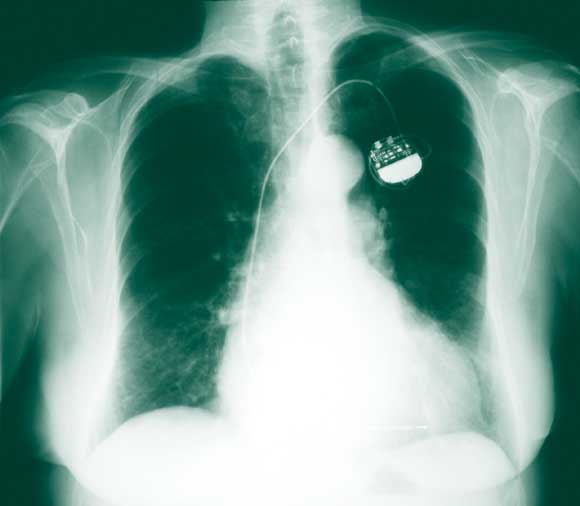

The patient’s medical record indicated that, 8 months previously, when she developed a cough, a chest x-ray had been performed by her physician. At around the same time, a routine check of the function of her pacemaker indicated that it was functioning normally. Re-examination of the x-ray revealed signs of lead erosion (Box 3) which had gone unnoticed. Thus, despite significant damage to the lead, pacemaker function may be unaffected.

Friction of the lead, most often against the clavicle and the first rib (known as subclavian crush) can damage the lead. The incidence of fracture of pacemaker leads is about 1.0%–2.5% and increases with the age of the lead.1 A way of avoiding this complication is to introduce the lead into the axillary or cephalic vein rather than via subclavian vein puncture.2,3

Routine chest x-rays should be performed to monitor the condition of pacemaker leads, especially where they cross the clavicle. We recommend an annual chest x-ray for pacemaker-dependent patients. This may identify lead damage that may not be apparent during a standard pacemaker check, and thus, potentially, avoid syncope or sudden death.